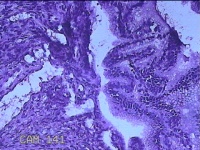

宫颈赘生物

性别

女

年龄

38岁

临床诊断

稽留流产

一般病史

停经2月余,阴道流血5天。

标本名称

大体所见

灰白粉红色不规则肿物1.5x1.2x0.3cm两个,表面糜烂,切开肿物呈实性,切面灰白粉红色,质软。

有可能调整一下拍照,部分区域看不清